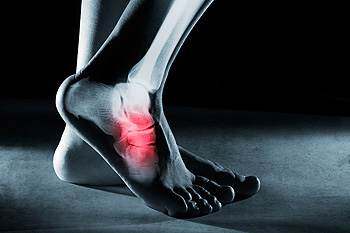

If a calcium deposit should forms between the arch of your foot and your heel, you may have a heel spur. This protrusion may grow gradually, and can be have a hooked, pointed, or even "shelf-like" appearance. Symptoms associated with this condition may include swelling, sharp pains in the heel and surrounding areas, or tenderness that is felt under the heel. If muscle and ligament strain damage the soft tissue in the heel, the result may the formation of a heel spur. Additionally, as the aging process occurs, the heel pads may not provide adequate shock absorption. The symptoms of heel spurs may be similar to those of plantar fasciitis, so it is advised to seek the counsel of a podiatrist who can properly diagnosis this condition.

Heel spurs can be incredibly painful and sometimes may make you unable to participate in physical activities. To get medical care for your heel spurs, contact Brent Harwood, DPM from Southeast Podiatry. Our doctor will do everything possible to treat your condition.

Heels Spurs

Heel spurs are formed by calcium deposits on the back of the foot where the heel is. This can also be caused by small fragments of bone breaking off one section of the foot, attaching onto the back of the foot. Heel spurs can also be bone growth on the back of the foot and may grow in the direction of the arch of the foot.

Older individuals usually suffer from heel spurs and pain sometimes intensifies with age. One of the main condition's spurs are related to is plantar fasciitis.

Pain

The pain associated with spurs is often because of weight placed on the feet. When someone is walking, their entire weight is concentrated on the feet. Bone spurs then have the tendency to affect other bones and tissues around the foot. As the pain continues, the feet will become tender and sensitive over time.

Treatments

There are many ways to treat heel spurs. If one is suffering from heel spurs in conjunction with pain, there are several methods for healing. Medication, surgery, and herbal care are some options.